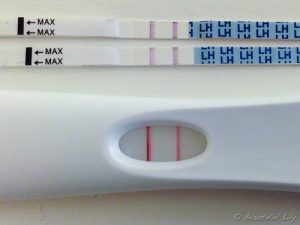

O teste de ovulação basicamente detecta um hormônio em abundância que faz o folículo romper e o óvulo sair para as trompas. O LH, hormônio luteinizante, em seus picos são capturados pelos anticorpos e reagentes existentes na tira de teste e fazem com que a linha de teste fique mais escura ou da mesma cor que a linha de controle. Caso a linha fique clara, então é sinal que o pico hormonal ainda não ocorreu.

O teste de farmácia complementa todos esses métodos de detecção. Os testes vendidos no Brasil têm cerca de cinco tiras e podem ser feitos durante todo o período fértil. Caso o teste não positive durante os dias que forem feitos, a mulher deve continuar a fazer mesmo que necessite de mais um kit de cinco testes. No entanto na grande maioria das vezes o teste chega a pegar o pico de LH sem maiores problemas. Esses episódios são isolados devido a ciclos com ovulação tardia.